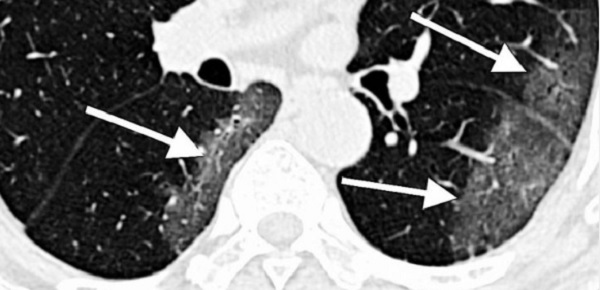

Các tính năng của phổi và tim bị nhiễm bệnh nhìn thấy trên hình ảnh y tế có thể giúp đánh giá mức độ nghiêm trọng của bệnh, dự đoán đáp ứng với điều trị và cải thiện kết quả của bệnh nhân. Tuy nhiên, một thách thức lớn là xác định nhanh chóng và chính xác các dấu hiệu này và đánh giá thông tin này kết hợp với nhiều triệu chứng lâm sàng và xét nghiệm khác. Mục tiêu của MIDRC là dẫn đầu sự phát triển và thực hiện các chẩn đoán mới, bao gồm các thuật toán học máy, cho phép đánh giá nhanh và chính xác tình trạng bệnh và giúp các bác sĩ tối ưu hóa việc điều trị bệnh nhân.

Nỗ lực thu thập một kho lưu trữ lớn hình ảnh phổi nhiễm COVID-19, theo tiến sĩ Guoying Liu giải thích, chương trình khoa học của NIBIB về nỗ lực này, cho phép các nhà nghiên cứu đánh giá cả dữ liệu mô phổi và tim, đặt câu hỏi nghiên cứu quan trọng và phát triển dấu hiệu hình ảnh dự đoán COVID-19 có thể được gửi đến các nhà cung cấp dịch vụ chăm sóc sức khỏe.